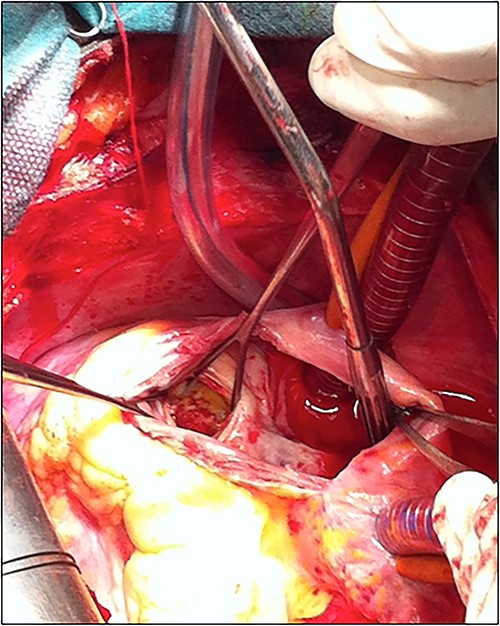

The patient underwent cardiac surgery with a median sternotomy approach and cardiopulmonary bypass. Exploration confirmed the presence of a giant aneurysmal formation originating from the LCX and communicating with the RA. After aortic clamping, a right atriotomy was performed. The aneurysm was opened, then both communications (to the LCX and the RA) were closed using two autologous pericardial patches. A third patch was used to close the aneurysm after partial resection (Fig. 5).

The patient was discharged after an uneventful postoperative course. The control TTE performed 2 weeks after the intervention showed that the right atrial shunt was gone (Fig. 6).